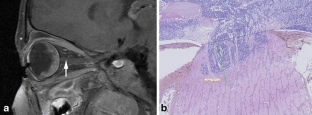

Relevance of CT and MRI in retinoblastoma for the diagnosis of postlaminar invasion with normal-size optic nerve: a retrospective study of 150 patients with histological comparison

To assess the accuracy of CT and MRI for the detection of postlaminar invasion in normal-size nerves.

A total of 150 patients enucleated for retinoblastoma were included. Imaging data (119 CT and 46 MRI) were retrospectively reviewed and compared with histological findings. Abnormal contrast enhancement of the optic nerve was used as diagnostic criterion for invasion. The associations between postlaminar invasion and several indirect signs were also assessed. Statistical analysis was performed with the Kruskal-Wallis and Fisher exact tests.

Postlaminar invasion on histology was observed in 8% (12/150). The sensitivity, specificity, accuracy and negative and positive predictive values were 60%, 95%, 91%, 95% and 60% for MRI, and 0%, 100%, 94% and 94% (PPV not assessable) for CT, respectively. Tumour diameter was the only indirect radiological sign significantly associated with postlaminar optic nerve invasion (P=0.002).

Our results suggest that MRI is more relevant than CT for preoperative detection of optic nerve invasion in patients with retinoblastoma. Tumour diameter is the only indirect sign significantly associated with postlaminar invasion.